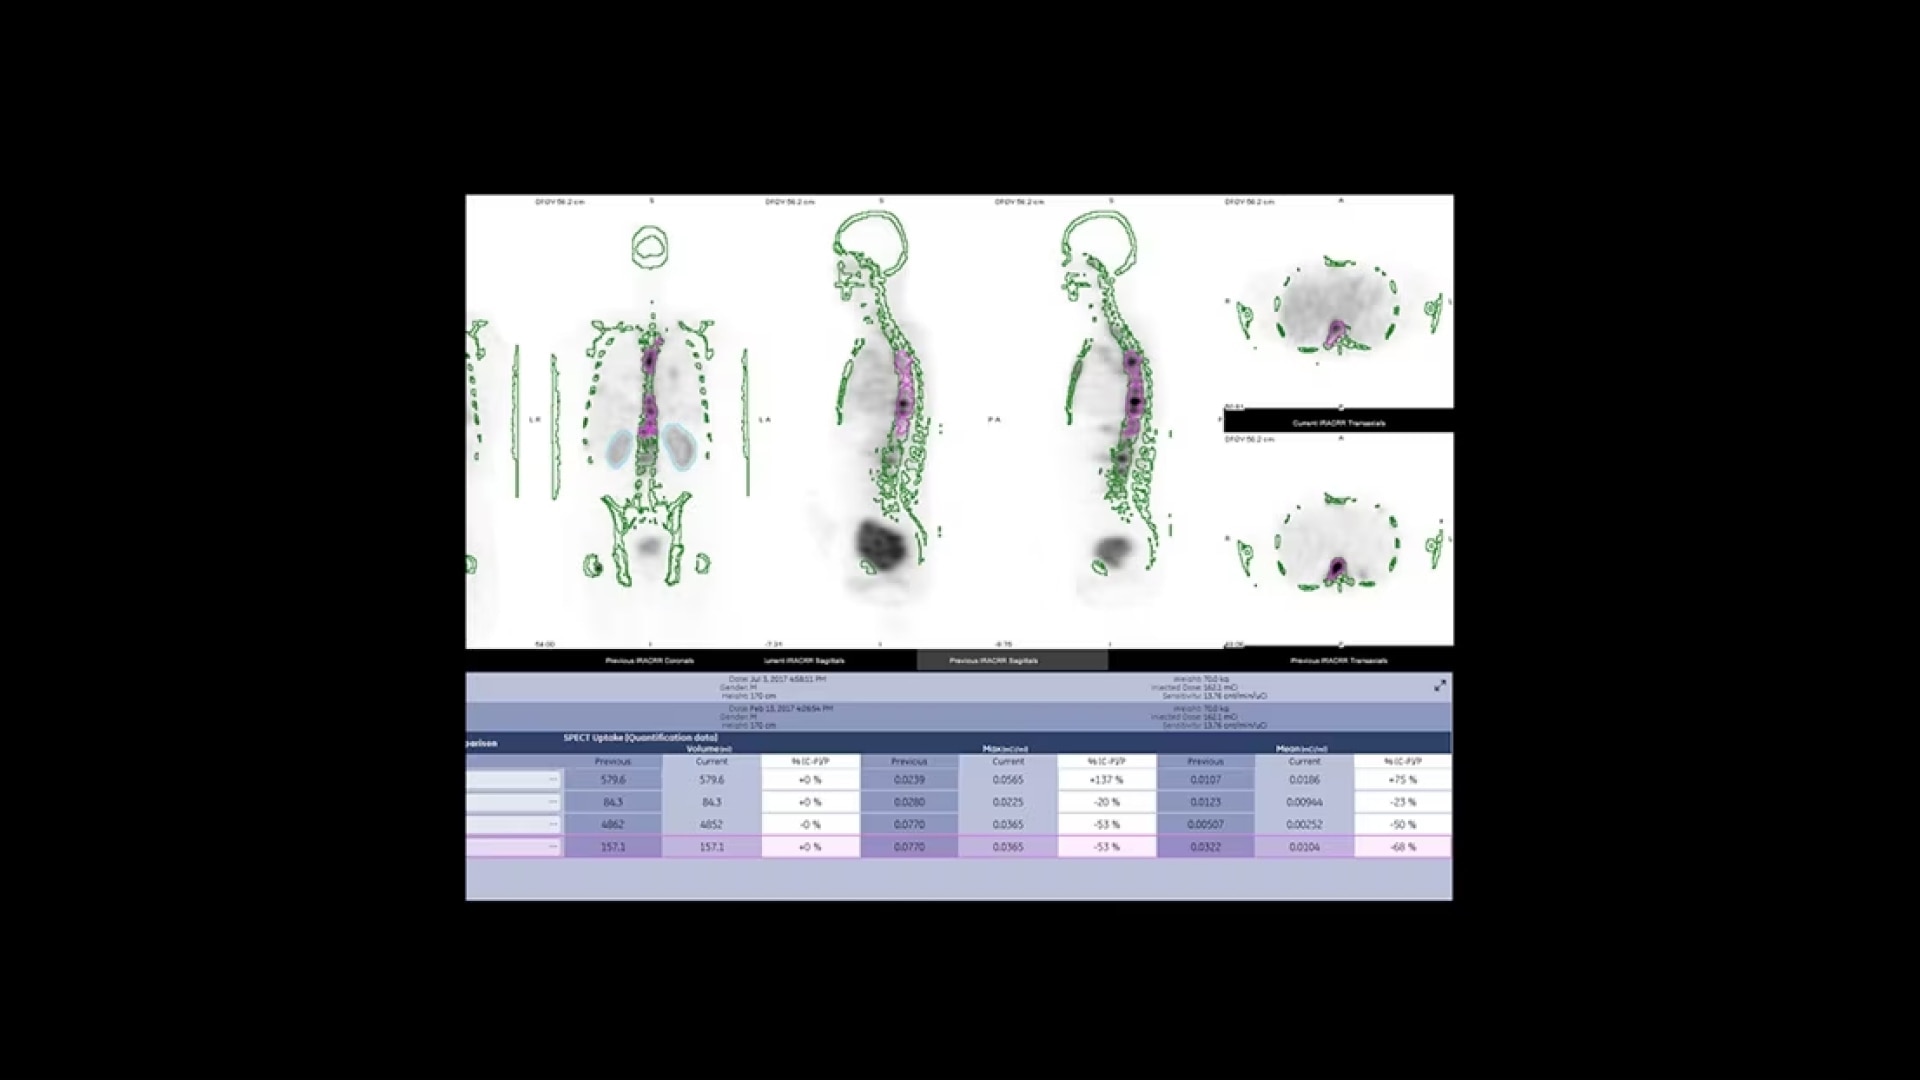

Additionally, this is a premium SPECT/CT system that delivers the added flexibility of a standalone CT that includes advancements in dose and metal artifact reduction. And it delivers the accurate, reproducible results referring physicians require in a comfortable and streamlined exam experience.